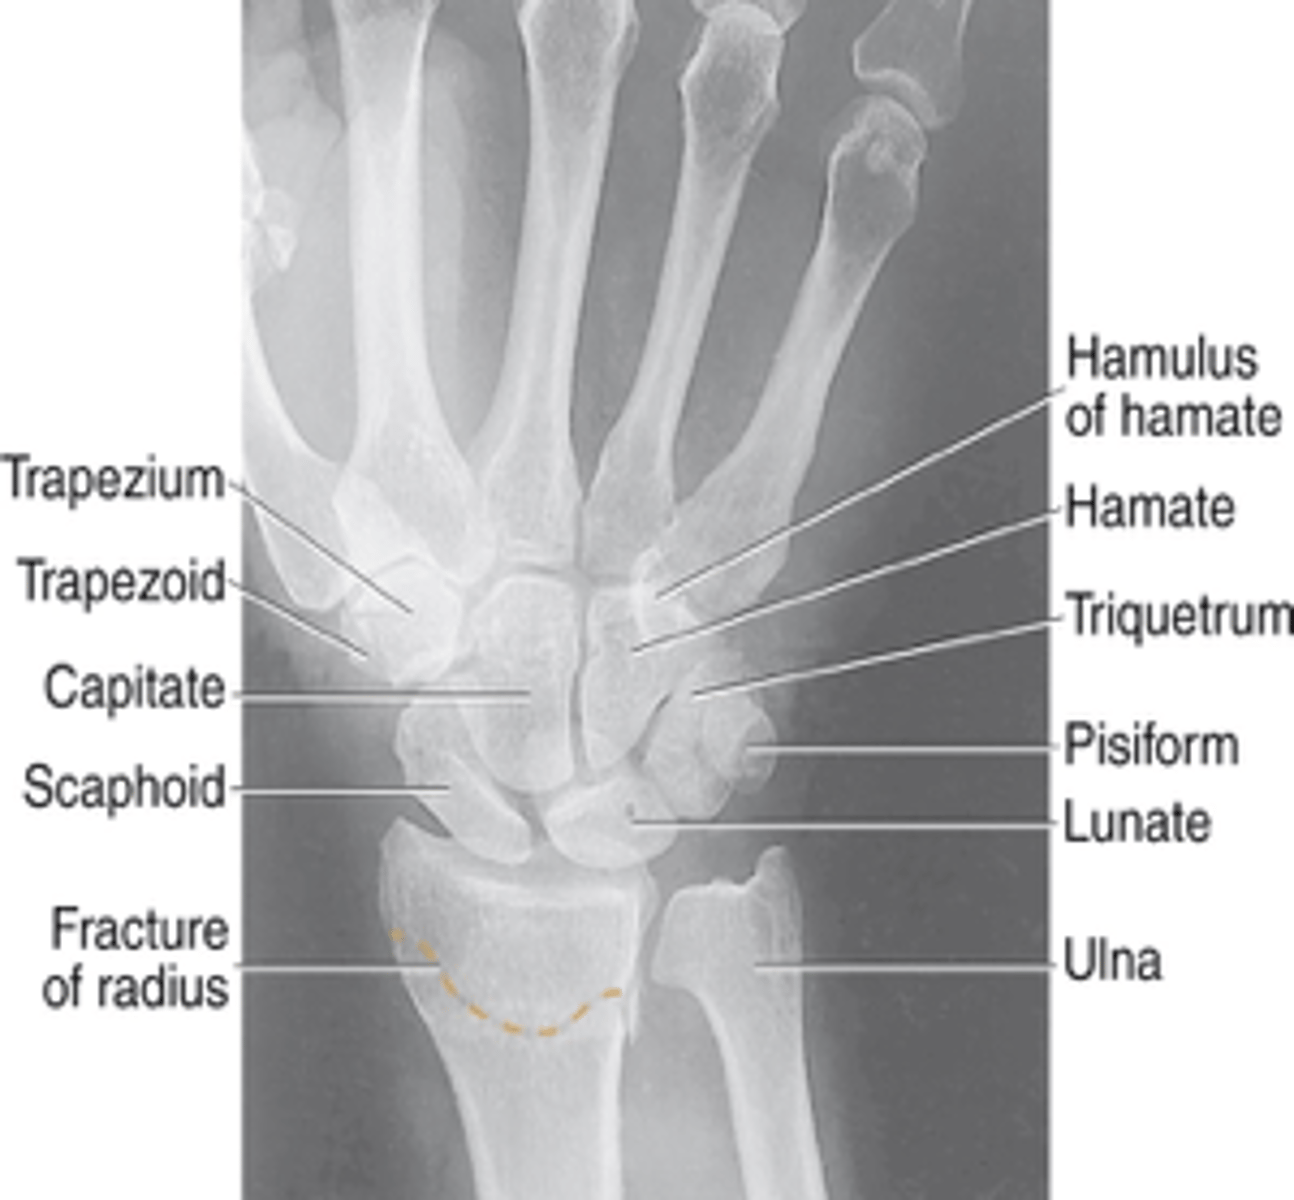

PA Wrist

PA Oblique Wrist

Lateral wrist